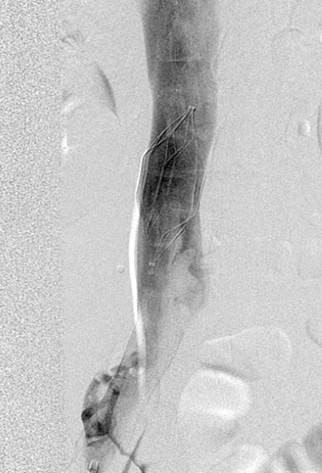

Venograma de la pierna izquierda donde se muestra un trombo oclusivo en las venas profundas más visualizadas.

Eliminación razonable del trombo en las venas ilíacas tras una sola pasada del catéter DVX de AngioJet (25 mg de tPA en 250 cc de solución salina normal).

Venograma final tras la aspiración con catéter grande y tratamiento de la estenosis subyacente (debido a la compresión extrínseca del tumor) con un stent de 16 mm con el balón inflado a 12 mm.

Tiempo total: <90 minutos. Flujo interno perfecto de la parte posterior de la rodilla a la vena cava inferior (VCI).